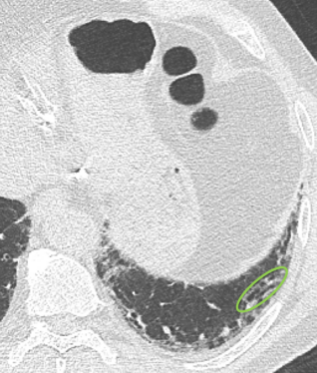

Der behandelnde Arzt hat sich für eine hochauflösende Computertomographie

(HRCT) des Thorax entschieden und folgende klinische Befundung erhoben:

Befundung des HRCT-Scans:

- Retikuläre Veränderungen

- Milchglasartige Dichteanhebungen

- Traktionsbronchiektasen

- Nicht vorhanden: Honigwabenmuster

CT: Computertomographie | HRCT: hochauflösende Computertomographie

10 Monate nach dem ersten Scan

CT bei der Erstpräsentation